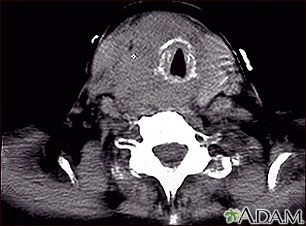

Tomografía computarizada de un tumor en la garganta, consecuencia de un cáncer tiroideo. Este tumor ha rodeado, constreñido y desplazado la tráquea.